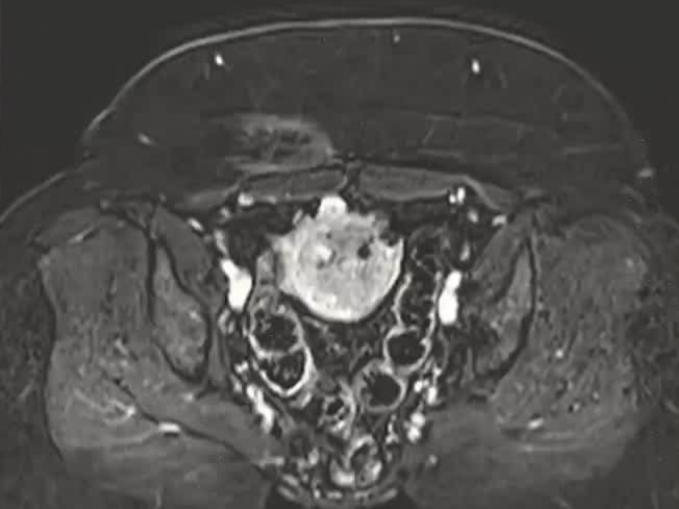

| 腹壁下病变 | MRI引导下 冷冻消融。装有热水的手套在皮肤表面保护皮肤 |

保护措施:几乎所有干预都需要辅助保护措施,其中水分离术(13/16,81.3%)和水分离术与温盐水填充手套的皮肤保护结合(9/16,56.3%)是最常见的保护措施。

极少的安全余量

采用冷冻循环(功率与持续时间)